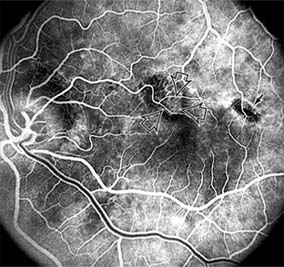

Nonexudative age-related macular degeneration is characterized by variable degrees of atrophy and degeneration of the outer retina, retinal pigment epithelium, Bruch's membrane and choriocapillaris. Of the ophthalmoscopically visible changes in the retinal pigment epithelium and Bruch's membrane, drusen are the most typical (Figure 10-1). Drusen are discrete, round, yellow-white deposits of variable size beneath the pigment epithelium and are scattered throughout the macula and posterior pole. With time, they may enlarge, coalesce, calcify, and increase in number. Histopathologically, most drusen consist of focal collections of eosinophilic material lying between the pigment epithelium and Bruch's membrane; they therefore represent focal detachment of the pigment epithelium. In addition to drusen, clumps of pigment irregularly dispersed within depigmented areas of atrophy may progressively appear throughout the macula. The level of associated visual impairment is variable and may be minimal. Fluorescein angiography demonstrates irregular patterns of retinal pigment epithelial hyperplasia and atrophy. Electrophysiologic testing in most patients is normal.

Figure 10-1

Figure 10-1: Age-related macular degeneration with discrete (small arrow) and large confluent (large arrow) macular drusen.